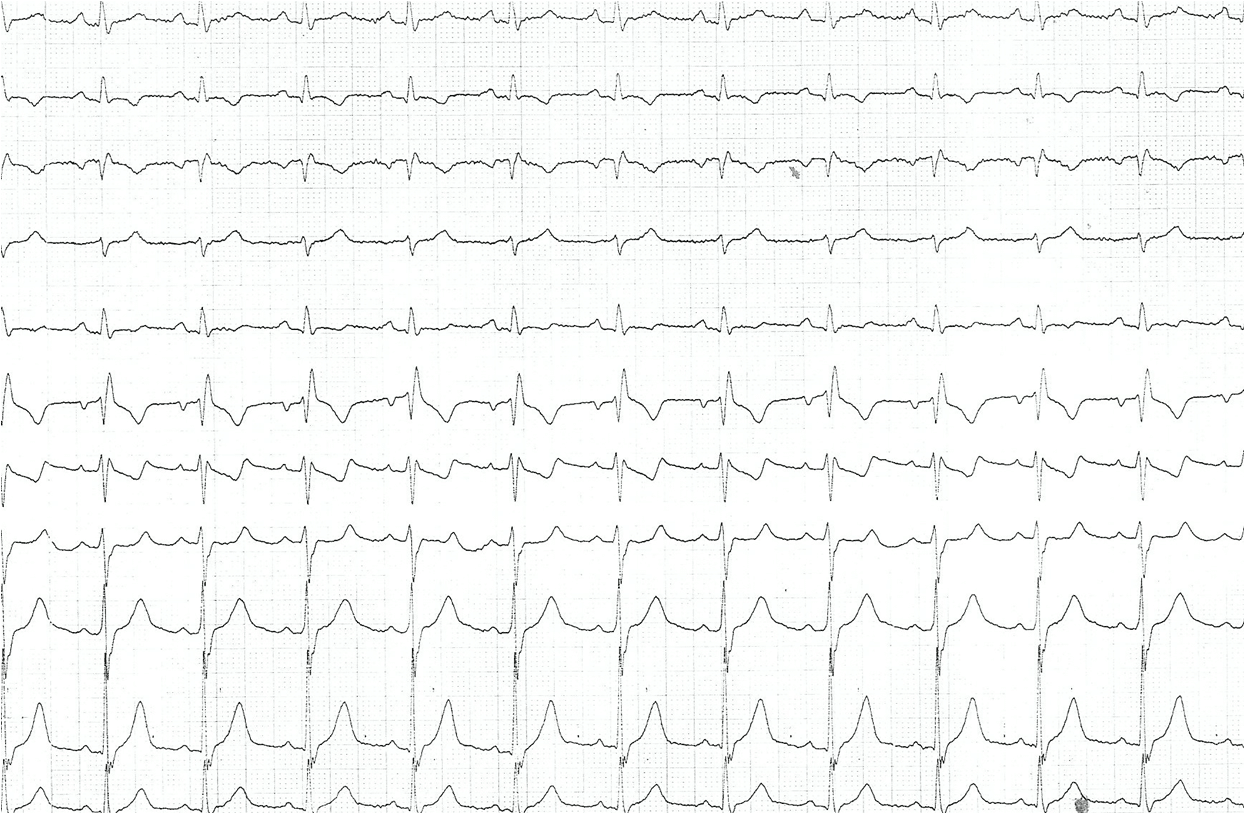

Evaluare la 3 luni